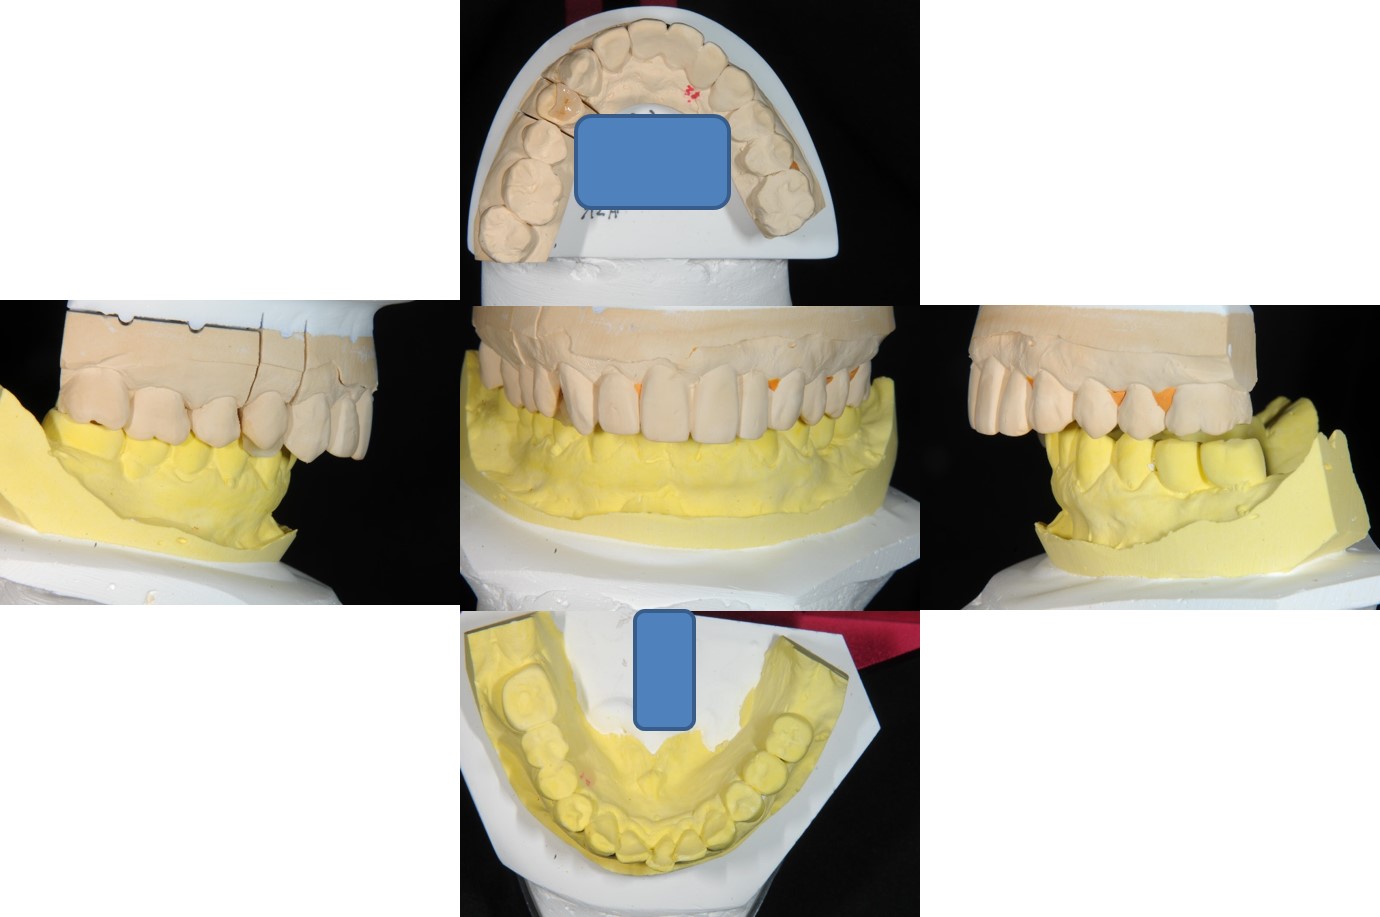

上面弓與咬合器

咬合器上製作瓷塊